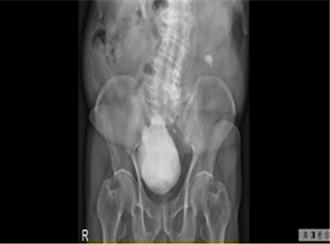

8旬男「尿不出来」竟是膀胱藏400克巨大结石

高雄市81岁谢姓男子长期有解尿困难问题,至建佑医院泌尿科求治,经检查才发现双侧肾结石及膀胱内竟有一颗重达400公克、直径超过10公分的「巨大结石」,经手术顺利取出,病人虽笑称「像生了一颗石头」,但也庆幸终于能畅快上厕所,为多年不适画下句点。